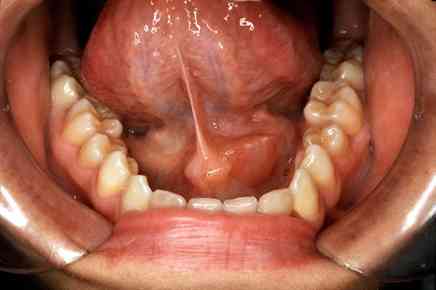

أسباب التهاب الغدد اللعابية يمكن أن يصاب الأشخاص بالتهاب الغدة اللعابية نتيجة العديد من الأسباب : انخفاض تدفق اللعاب بسبب بعض الحالات الطبية مثل جفاف الفم وقلة نظافة الفم، مما يزيد من نمو البكتيريا. ... اقرأ المزيد